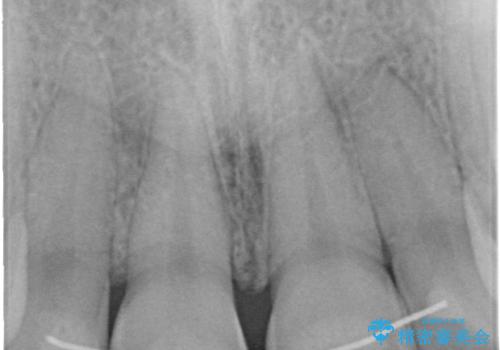

- 前歯をきれいにしたいとのご希望がありました。

生まれつき歯の色が白濁しているところや、黄色くなっているところがあり、セラミッククラウンに審美的改善を行うこととしました。